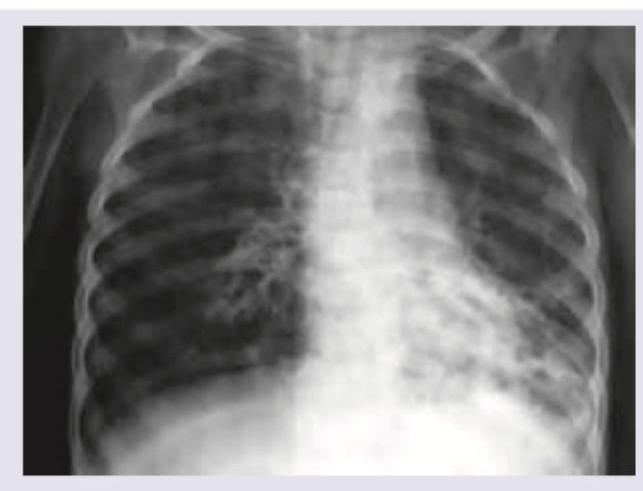

Explanation: ***Bronchiectasis*** - The X-ray shows diffuse, bilateral **peribronchial thickening** and **cystic lucencies**, particularly in the lower lobes, which are classic signs of bronchiectasis in a patient with cystic fibrosis. - **Bronchiectasis** is a common and progressive complication of cystic fibrosis due to recurrent infections and inflammation leading to permanent dilation and damage of the bronchi. *Left lower lobe pneumonia* - While pneumonia can occur in cystic fibrosis, the image demonstrates chronic changes rather than an acute consolidation typically seen with **left lower lobe pneumonia**. - **Pneumonia** would typically present with a more focal area of increased density, possibly with air bronchograms, which are not the predominant features here. *Bronchopneumonia* - **Bronchopneumonia** would show patchy areas of consolidation scattered throughout the lungs, often involving multiple lobes. - While there are opacities, the prominent **cystic changes** and **tram track lines** are more indicative of bronchiectasis than acute bronchopneumonia. *Right middle lobe collapse* - **Right middle lobe collapse** would manifest as a triangular opacity in the right mid-lung field, often associated with a shift of the right heart border and horizontal fissure. - This specific pattern of collapse is not observed; instead, there are generalized changes consistent with diffuse airway disease.